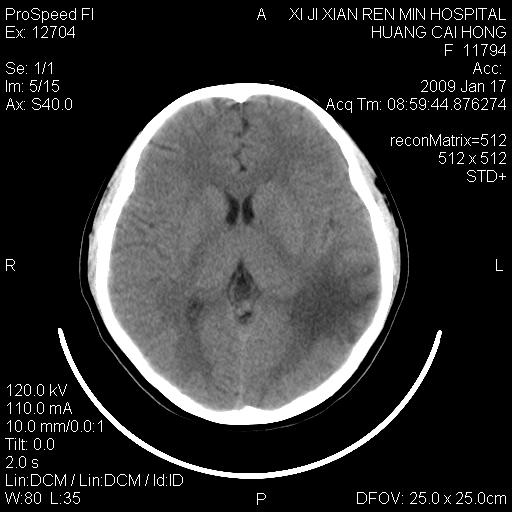

以下是引用zbp537在2009-1-19 13:54:00的发言:[br]首先考虑脑炎。[br]诊断依据:[br]1、患者较年轻。[br]2、有感冒病史。[br]3、左侧颞枕叶这么大一片低密度影,占位征象却不明显,不符合肿瘤特征,其内的高密度影为出血灶。

以下是引用xiaoniu在2009-1-19 13:29:00的发言:[br]左侧颞叶三角形低密度影,占位效应不明显,其内点片样高密都影,青少年患者,首先考虑:少突胶质瘤。因为有感冒病史,不能除外感染的可能。